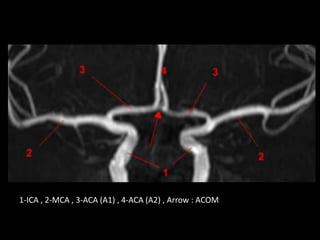

b) Segmental Anatomy :

-A1 segment : from the ICA bifurcation to the ACOM

14mm in length

-A2 segment : from ACOM to the origin of the

callosomarginal artery (the junction of the rostrum and

genu of the corpus callosum)

-A3 segment : distal to the origin of the callosomarginal

artery “a.k.a. pericallosal artery “ (extends around the

genu until the artery turns sharply posteriorly)

-A4 and A5 segments : above the corpus callosum are

separated by the plane of the coronal fissure

1-ICA , 2-MCA , 3-ACA (A1) , 4-ACA (A2) , Arrow : ACOM